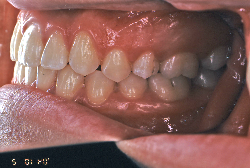

叢生(そうせい)

凸凹な歯並びのことを叢生といいます。矯正歯科に来院する患者様の主訴の中で、最も多いのが「配列の凸凹を真っ直ぐにしたい」というものです。歯の大きさと顎の大きさの調和がとれていないことが原因です。

凸凹を主体としたケースの場合、当院の平均治療期間は18ヶ月ですので、このケースは少し長めに経過しました。理由の一つは凸凹の程度がかなり重症だったと言うことですが、もう一つは、右下第2大臼歯が45度くらい前傾していたため、それを整直化させるために時間を要したと考えています。いずれにしても最終結果は大変よい状態と思います。

治療前は並びが乱れて見た目が悪いというのはもちろん問題ですが、歯科医学的に一番困るのは噛み合わせが悪いという点です。上下の犬歯(3番目の歯)は、上下的に離れた位置にあるため接触することができません。つまり歯としては存在していても、歯としては機能していないということです。